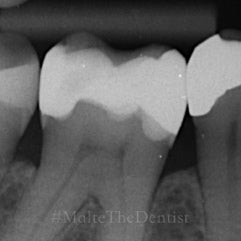

Underviser: Malte Heinrich

Fokus er på alt det, der skal sidde i kroppen, før posterior komposit bliver stabilt, effektivt og forudsigeligt i hverdagen.

• Carieseksavering med omtanke

• Form, anatomi og workflow, der gør dine fyldninger hurtigere og bedre